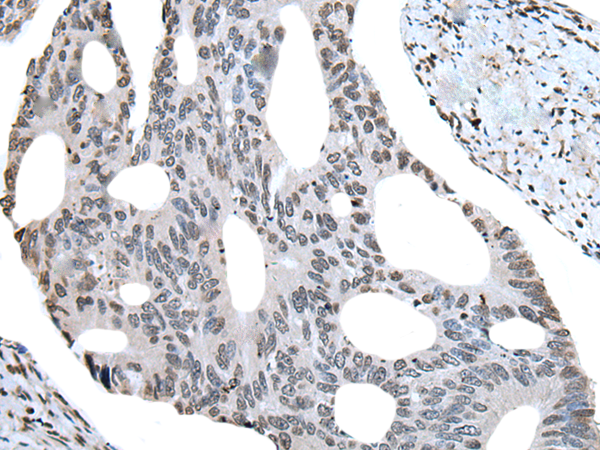

The image is immunohistochemistry of paraffin-embedded Human colorectal cancer tissue using P12946(BHLHA15 Antibody) at dilution 1/25. (Original magnification: ×200) |